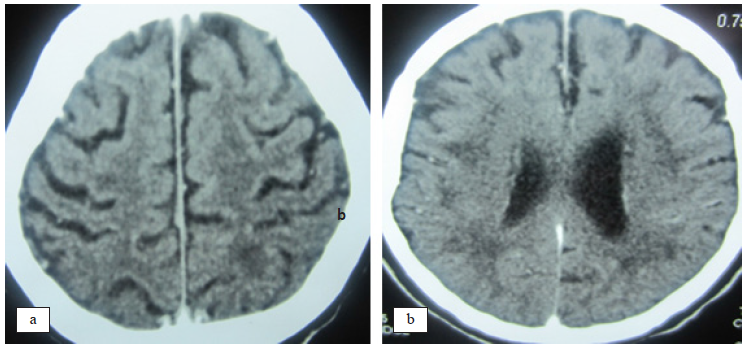

Investigación con neuroimágenes

Con el propósito de determinar el compromiso grave del estado neurológico del paciente, que explicara los severos defectos cognitivos, los trastornos comportamentales y los diferentes tipos de epilepsia que habían acaecido durante décadas del desarrollo de la enfermedad, se efectuaron estudios con tomografía cerebral, resonancia magnética del cerebro y estudio angiográfico del sistema carotídeo y vertebro-basilar. Figura 2

No existe la menor duda con respecto al diagnóstico de EB en ambas presentaciones, al referirnos a las manifestaciones aftosas, así como a las asociaciones con patología vascular autoinmune en los miembros inferiores. Los resultados en el LCR (pleocitosis linfocítica con proteinorraquia), igualmente los trastornos neurológicos encefálicos y medulares permiten conceptuar, en ambos casos, como afectos de NB. En el paciente varón la cefalea crónica, las diferentes formas de epilepsia, los trastornos progresivos de la función cognitiva hasta llegar a la demencia, la distimia depresiva, alternante con episodios de euforia, delirio paranoide, constituyeron las manifestaciones neurológicas y psiquiátricas que complementadas con los hallazgos en las neuroimágenes TEM y RMC, que muestran lesiones compatibles con angiopatía vascular isquémica crónica, constituyen el subgrupo parenquimatoso de la enfermedad (NB) (4), desarrollados en el lapso de 34 años. Debemos de precisar que los hallazgos en el líquido cefalorraquídeo y los de las neuroimágenes son similares a los descritos en la literatura.